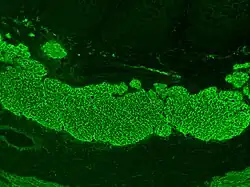

Current medical guidelines recommend testing tissue transglutaminase 2 immunoglobulin A (TTG IgA) in those with suspected coeliac disease.[53][54] Because IgA deficiency is more common in those with coeliac disease,[55] guidelines recommend testing for IgA deficiency as a part of the diagnostic workup for coeliac disease. If an individual with IgA deficiency is getting tested for coeliac disease, immunoglobulin G (IgG) based tests such as deamidated gliadin peptide IgG (DGP IgG) or endomysial antibody (EMA) can be used instead of IgA-based tests.[53][54] Antigliadin antibodies (AGA) and antireticulin antibodies (ARA) were historically used to test for coeliac disease, however due to the development of more accurate tests, they are no longer recommended.[7][55] Due to the risk of false positive or negative serological tests and the consequences of leaving coeliac disease untreated or introducing unnecessary dietary restrictions in the case of a false positive, biopsies are used to confirm the diagnosis regardless of blood tests.[7][54]

TG2 IgA has a high sensitivity (92.8%) and specificity (97.9%), is cost-efficient and widely available, making it the first choice for serological tests in the diagnosis of coeliac disease.[56][51] Performance of the TG2 IgA test differs between labs and no formal standardisation between assays exists.[10] The severity of small intestine damage generally correlates with the levels of TG2 IgA found in the blood, meaning that the sensitivity is lower in people who have less damage to their intestines.[56][55] EMA has a lower sensitivity, but its specificity is near 100%;[56] it can be used to confirm coeliac disease in those who have borderline TG2 IgA levels.[51] EMA testing is costly, hard to interpret and vulnerable to interobserver and inter-site variability.[10][57] DGP IgG is used to evaluate coeliac disease in those with IgA-deficiency. Coeliac disease is more common in those with IgA-deficiency, so medical guidelines recommend that people being tested for coeliac disease are also tested for IgA-deficiency. Because IgA-based tests are unreliable in those with IgA deficiency, IgG-based tests are used instead. These include EMA IgG, DGP IgG, and TTG IgA, which are less accurate than IgA testing.[55][58]